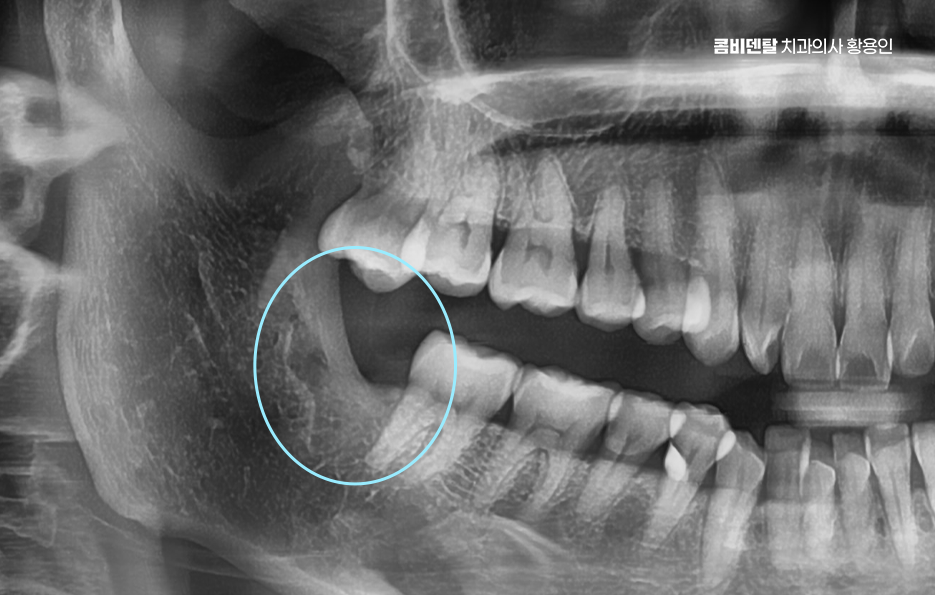

그 이유는 아래턱 뼈가 위턱보다 단단하고 밀도가 높아서 치아가 쉽게 안 빠지고, 하치조 신경도 가까이 있기 때문이고 매복된 사랑니일수록 치료가 까다로워질 수 있다는 점에서 사랑니 발치 경험이 많은 치과의사를 잘 만나는 것도 중요한 거예요

아래 사랑니 발치 통증에 대해 먼저 치료 과정을 살펴보면 발치 중에는 국소마취를 하기 때문에 통증은 거의 느끼지 않지만 사랑니가 깊게 매복되어 있다면, 마취 범위가 넓어져야 하고 시술 시간도 길어지니까 그에 따른 압박감이나 두려움이 커질 수는 있어요.

보통 발치 후에는 마취가 풀리면서 통증이 생길 수 있는데 보통 하루에서 삼일 사이가 가장 통증이 심하고, 이후부터는 점점 가라앉는 경과를 보이지만 개인에 따라 회복 속도나 통증 민감도가 다르기 때문에, 일주일 이상 불편함을 느끼는 경우도 있으며 특히 매복사랑니의 경우에는 잇몸 절개 범위와 치료의 정확도, 시술 시간 등에 따라서도 아래 사랑니 발치 통증이 달라질 수 있기 때문에 경험 많은 치과의사와 함께하는 것이 시술 과정에서의 통증을 줄이는데 도움이 될 수 있어요